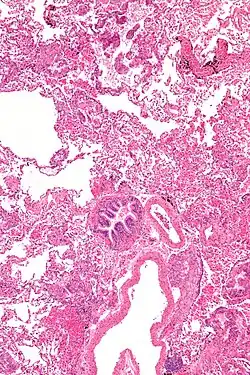

La destrucción pulmonar en LAM es una consecuencia de la infiltración difusa por células neoplásicas similares al músculo liso que invaden todas las estructuras pulmonares, incluidos los vasos linfáticos, las paredes de las vías respiratorias, los vasos sanguíneos y los espacios intersticiales.[13] Las consecuencias de la obstrucción de los vasos y las vías respiratorias incluyen acumulaciones de líquido quiloso, hemoptisis, obstrucción del flujo aéreo y neumotórax. El curso típico de la enfermedad muestra disnea progresiva con el esfuerzo, espaciada por neumotórax recurrentes y, en algunos pacientes, derrames pleurales quilosos o ascitis.[14]

La LAM puede requerir atención médica de varias maneras, la mayoría de las cuales desencadenan una tomografía computarizada de tórax. Los cambios quísticos de paredes delgadas en los pulmones pueden encontrarse incidentalmente en tomografías computarizadas del corazón, el tórax o el abdomen (en los cortes que incluyen las bases pulmonares) obtenidas para otros fines. Las TCAR de pacientes con CET revelan que aproximadamente el 20 % de las mujeres presentan cambios quísticos a los 20 años y aproximadamente el 80 % de las mujeres presentan cambios quísticos después de los 40 años.[28] En ocasiones, la LAM se detecta mediante una TC de tórax en pacientes que presentan un neumotórax espontáneo primario aparente, pero con mayor frecuencia no se solicita la TC (en los Estados Unidos) hasta que se producen recurrencias. La disnea progresiva con el esfuerzo sin las exacerbaciones y remisiones que son características del asma o la EPOC a veces requieren una tomografía computarizada de tórax. Una revisión de la TC por un experto familiarizado con LAM puede aumentar la precisión del diagnóstico.[29] El quilotórax también puede llamar la atención sobre LAM.